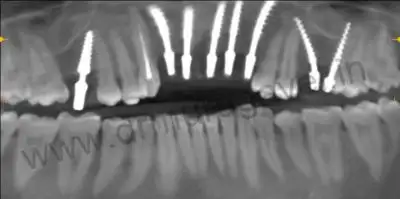

X RAY- after treatment

1.Permanent zirconia bridge in upper front region and left upper first molar 26

2.Tooth preparation in right upper canine 13; root canal treated tooth and zirconia crown

3.One basal implant in relation to missing right upper molar 16 , and CAD CAM crown for 6 months